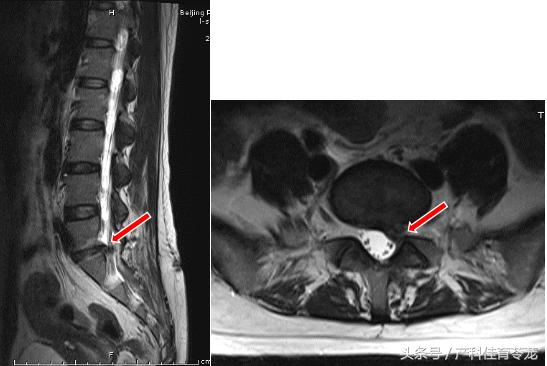

术前腰椎核磁显示第5腰椎和第1骶椎间盘脱出,游离,压迫神经。